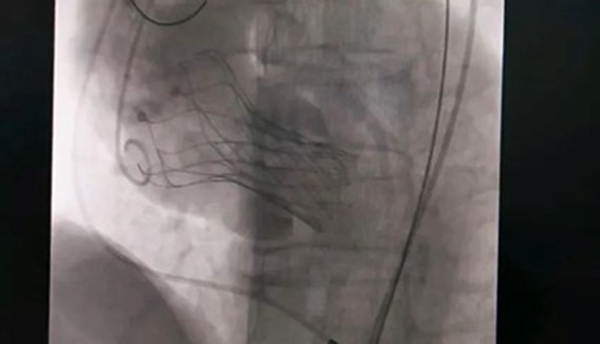

10月18日,該患者實施手術,在新橋醫院專家的指導下,心血管內科主任宋明寶帶領團隊把瓣膜置入心臟。

人工瓣膜置入中。重慶西區醫院供圖